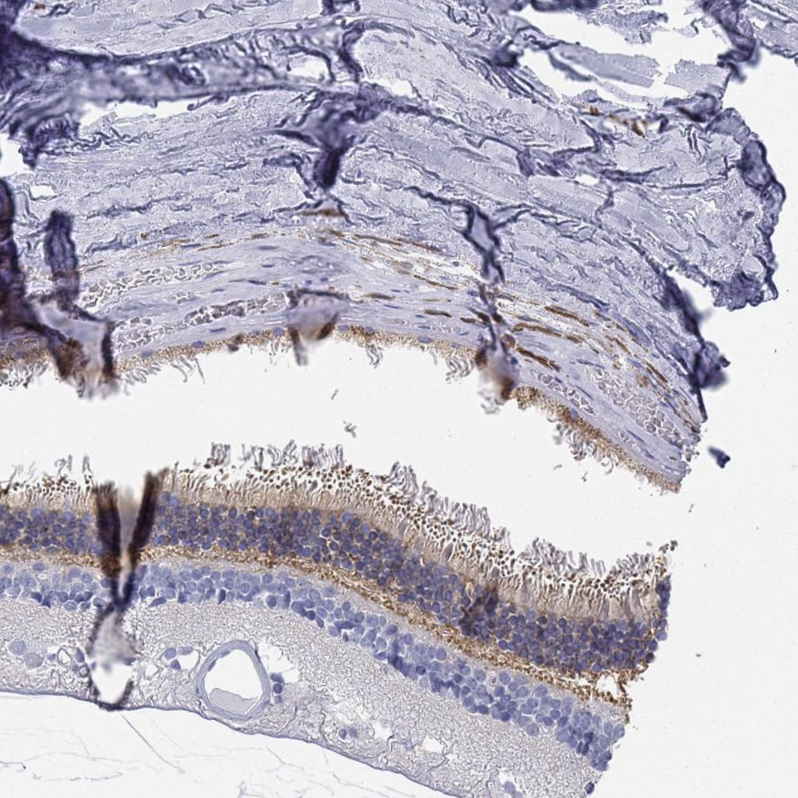

Immunohistochemical staining of human cerebellum shows moderate cytoplasmic positivity in Purkinje cells.